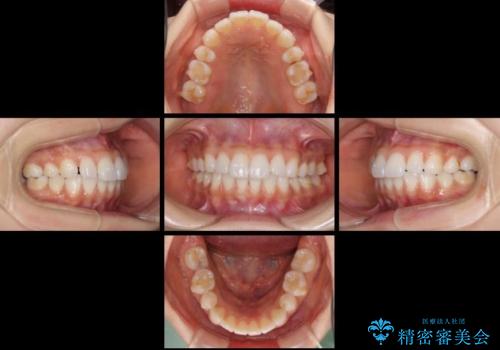

矯正治療の後戻り インビザラインによる再矯正治療

- 以前ワイヤー装置にて行った抜歯矯正の後戻りを気にして来院された患者様です。

前歯のデコボコにより、やや口元が突出した印象となっていたため、口元も引っ込めることとしました。

上下顎前歯に積極的にIPR(歯と歯の間を削る)を行い、インビザラインを用いて治療していくこととしました。

デコボコが解消されるのはもちろんのこと、突出感のあった前歯を引っ込めることができ、患者様には大変満足していただきました。